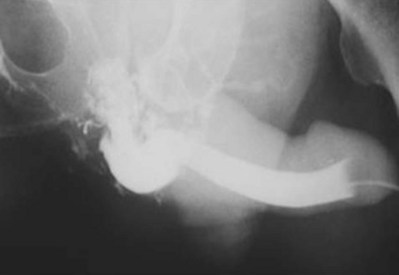

When blood at the urethral meatus is discovered, an immediate retrograde urethrogram should be performed to rule out urethral injury (Fig. 88–15). A small-bore urethral catheter (16 Fr) is placed unlubricated 1 cm into the fossa navicularis, and the balloon is filled with 1 cm of water to achieve a snug fit (Sandler and Corriere, 1989). Alternatively, a Brodney clamp or rolled gauze bandage can be used to provide penile traction. Patients should be placed in an oblique or lateral decubitus position, and it is preferable to perform the study under fluorography when it is available; 25 mL of contrast medium is injected gently by a 60-mL catheter-tip syringe, and the film is taken during injection. Direct inspection by urethroscopy is suggested in lieu of urethrography in females with suspected urethral injury (Perry and Husmann, 1992; Koraitim, 1999).